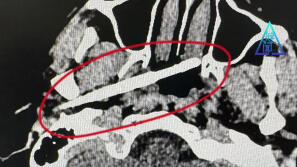

44 岁男子晨起走路 “飘” 仍赴宴,突发中风!